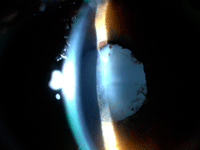

8 (

Figura 1).

Figura 1. Uveítis postquirúrgica tras facoemulsificación en niño con catarata secundaria a pars planitis.